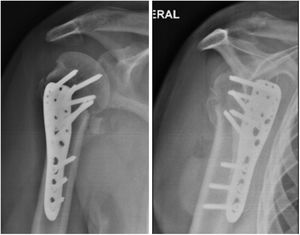

Fue inmovilizado con cabestrillo durante el primer mes. Inició fisioterapia al mes siguiente de su intervención quirúrgica trabajando manejo del dolor y edema, recuperación de la movilidad articular, fuerza de la extremidad y actividades básicas cotidianas, el paciente solo logró realizar 20 sesiones de fisioterapia. Cada mes se realizó rayos x de control (fig. 4) con evaluación por parte de ortopedia mostrando buena evolución. A los 6 meses post quirúrgico el paciente muestra evolución satisfactoria (figs. 5 y 6). Dolor leve a las rotaciones clasificado en 1 según escala análogo del dolor, movilidad articular: eleva hombro a 140°, abducción de 115°, rotación externa 20° rotación interna hasta T12. Consolidación de la fractura satisfactoria sin déficit neurovascular, con una puntuación en cuestionario DASH de 1.6